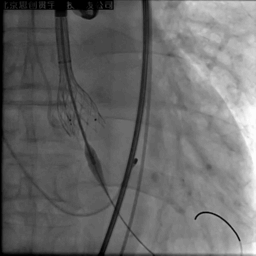

主动脉根部造影

20mm球囊预扩

第一次释放,瓣膜位置偏高

应用PLUS回收支架,重新定位